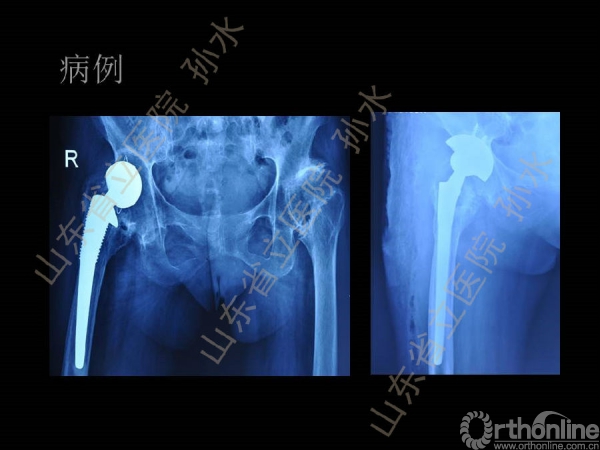

孙水:Jumbo-Cup在髋关节翻修中的应用